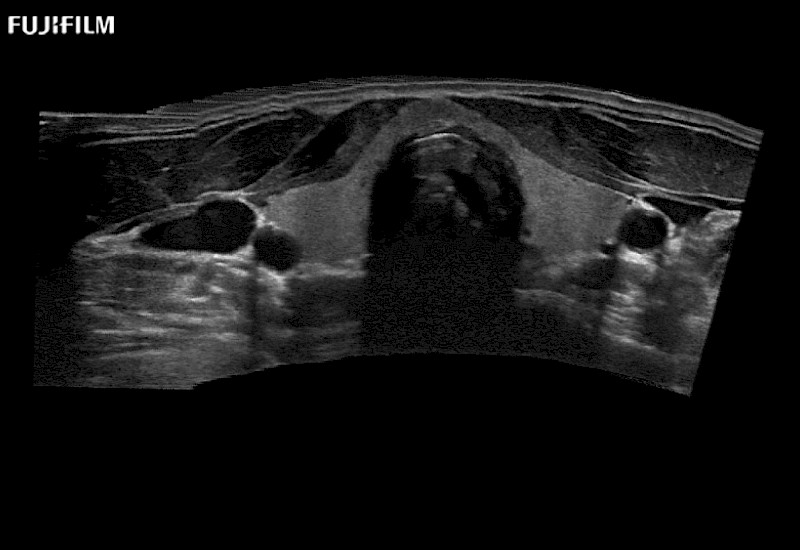

Extraordinary high-resolution digital imaging

for use during open and laparoscopic procedures: Tumor localization & staging, Ablation, Resection, Biopsy, Transplant, Abdominal exploration, Robotic surgery

- Instant feedback on tumor margin delineation

- Valuable information to guide tumor resections

- Exceptional near and far-field resolution

- Instant feedback on tumor margin delineation